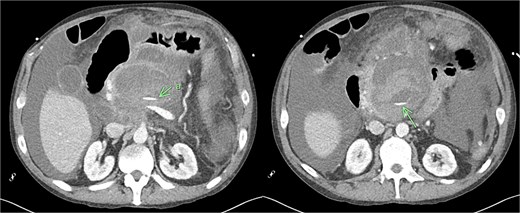

Despite the absence of abdominal symptoms, a computed tomography of the abdomen and pelvis (CTAP) was performed due to markedly elevated lipase levels. The CTAP (Figs 3–5) revealed evidence of acute pancreatitis (Fig. 5, arrow), with a complex peripancreatic fluid collection (Fig. 3, arrow). Additionally, a focal thrombus was observed within the portal venous confluence (Fig. 4, arrow). Further ultrasound of the gallbladder was negative for gallstones (Fig. 6), ruling out gallstone-induced pancreatitis.

CTAP coronal view; focal thrombus within the portal venous confluence (arrow).